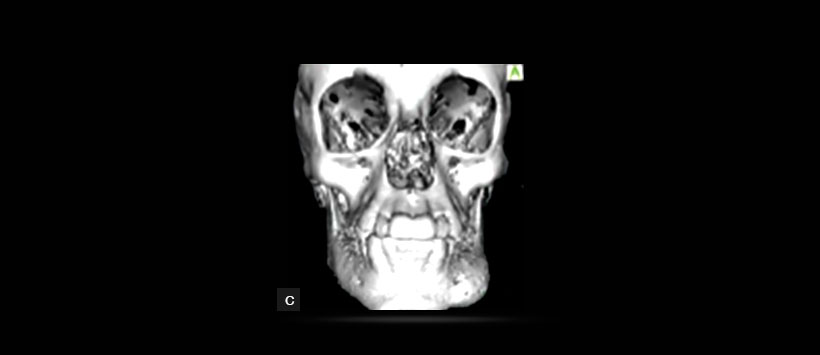

Figura 4: Renderizado 3D de la TCHC que muestra la asimetría ósea a nivel de la zona mandibular izquierda.